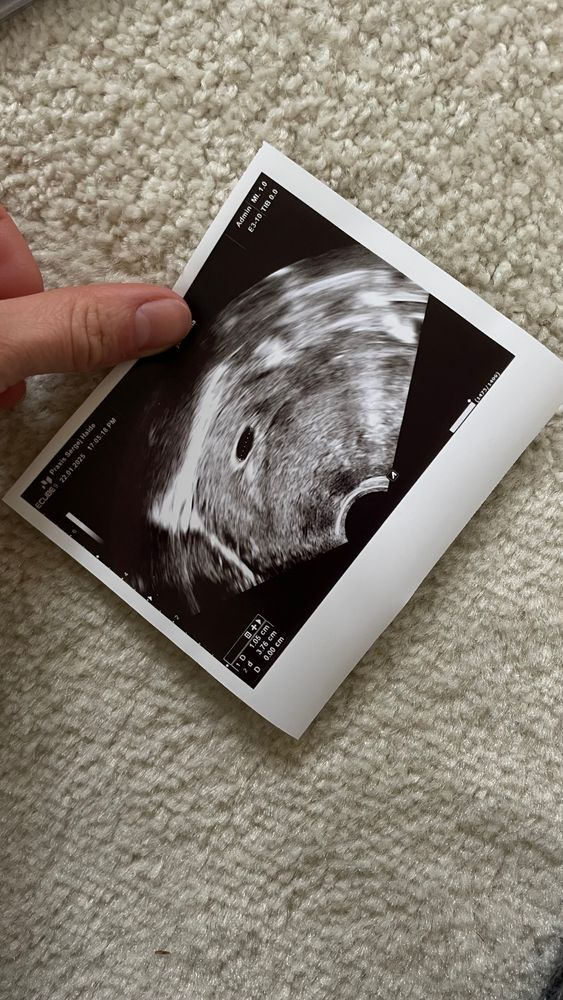

Аааааааа, я так понимаю, что у меня 1,01 внизу там стоит это и есть размер плодного яйца ?

Аааааааа, яйцо 20,4. Эмбрион 10,3. Так что увидят

Если овуляция позже , чем на 14 день , то рано .

10 мм всего плодное яйцо . У вас поздняя овуляция , похоже .

Эмбрион начинает просматриваться на узи в 4 недели от овуляции,6 недель по месячным это с нормальной овуляцией(14 д.ц) это как раз и есть ровно 4 недели от овуляции,но если овуляция была к примеру на 18 д.ц, соответственно в 6 акушерских уже не будет 4 недели от овуляции,а меньше 3,3 только соответственно эмбрион не найдут,так как рано,судя по хгч в 1 д.з у вас там не 15 дпо,а 12 примерно,значит овуляция позже была и срок меньше